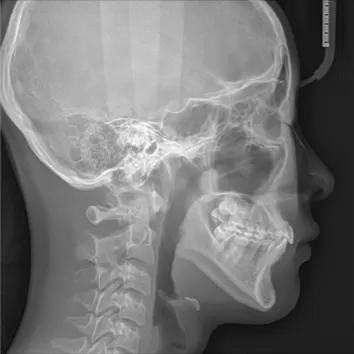

Rayons X avant le traitement

[Radiographie panoramique/Céphalogramme latéral]